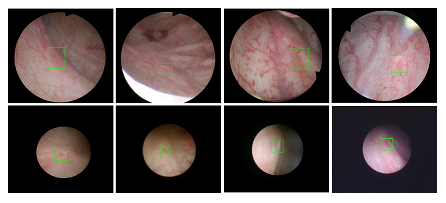

PO18 医疗机器人研究院—深睿医疗人工智能医学视频联合实验室成立于2018年7月。PI包括来自于交大生医工学院和电院的三位教授,平台建设目标是将人工智能实时地用到临床医学中去,研究方向包括:1. 建立内窥镜人工智能辅助诊断系统,通过对病灶和解剖结构的实时识别来辅助医生更好地进行微创诊断和治疗;2. 以个性化、定量化的精准诊疗技术为研发目标,重点开展医学影像智能诊断、医学可视化及计算机辅助手术规划、AI及大数据分析在临床诊疗流程中的集成应用等方向的研发。试图利用AI技术、大数据分析技术、3D打印技术、虚拟现实及增强现实技术促进临床的影像诊断、治疗方案设计、预后预测分析等诊疗环节的智能化提升与技术变革;3. 面向运动医学康复、神经退行性疾病量化诊断,以及其他与人体运动相关的疾病诊疗、康复应用,开展视觉三维人体运动的测量、分析与识别研究,通过基于深度学习的视觉检测识别以及相关大数据分析,为相关疾病的诊疗和康复提供AI辅助。具体临床应用包括:关节镜手术术后康复指导和评估、帕金森病的量化诊断、精神疾病的量化诊断与评估、儿童异常行为分析等。

近年来,联合实验室发展了泌尿镜手术实时识别技术,人体姿态精确识别技术,另外围绕小儿先心病手术、肝癌消融手术、数字口腔诊疗的智能化提升等内容进行应用研发。